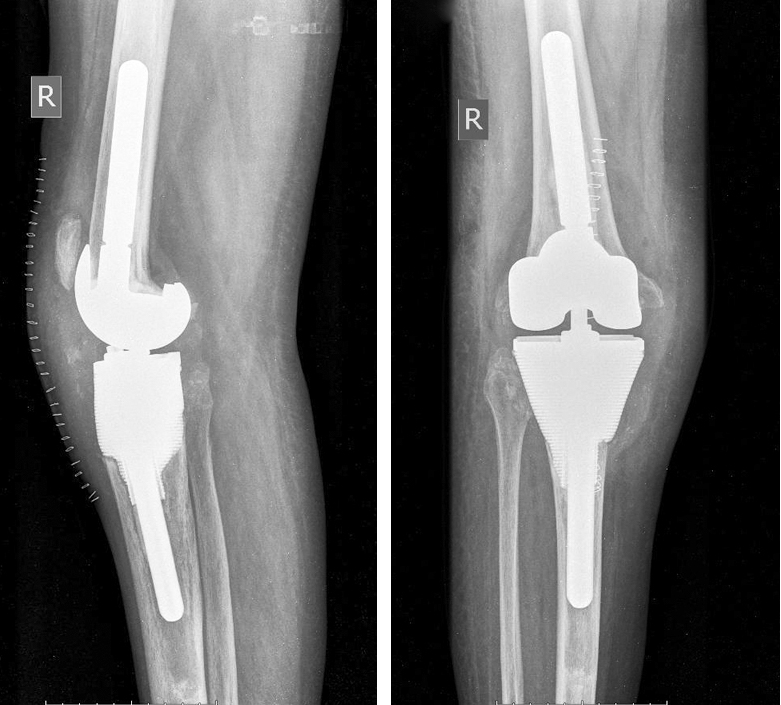

Спустя 12 мес. после операции болевой синдром отмечался только при значительных нагрузках. Пациентка передвигалась с помощью трости на расстояние более 3 км. Объем движений в коленном суставе немного увеличился и составил 0/0/95º. Сохранялся дефицит активного разгибания до 10º. На рентгенограммах признаки расшатывания эндопротеза или индивидуального имплантата не обнаружены, все компоненты стабильны (рис. 6). Спустя год после операции прослеживалась положительная функциональная динамика: результат по шкале KSS составил 69 баллов (удовлетворительный), по шкале WOMAC — 30 баллов (удовлетворительный), выраженность болевого синдрома по VAS — 1 балл.

Рис. 6. Послеоперационные рентгенограммы коленного сустава в прямой и боковой проекциях с индивидуальным титановым аугментом